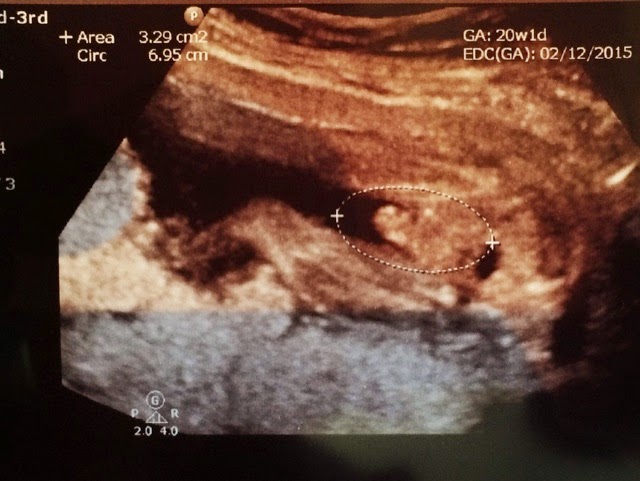

We found out last week that we are expecting an adorable baby boy. It was so much fun to find out this time and to have Adia, Isla, and my parents with us. As soon as the ultrasound tech zoomed in on his "area," I could tell automatically. I asked, "Is that what I think it is?" And it sure was what I thought it was.... She confirmed that he is definitely a boy and we all smiled, laughed, and just burst into excitement. I told the girls, "Did you hear that? Mommy is having a boy!" Adia smiled and Isla said, "Ooooooh!" In the beginning of my pregnancy, I kind of thought it was a girl, but I think a big part of that is because that was all I was used to and I have several friends who have 3 girls in a row. As I started feeling movement, I started to wonder if maybe this was a boy. He does not move as frequently as the girls and not nearly as intense as Isla. I think he is just a chill little guy like his daddy. In the ultrasound, he had his hands folded and his feet crossed and was just chillin' most of the time. In Isla's ultrasound, she NEVER stopped moving. Most of her pictures were blurry because she would not stay still (which was a huge indicator of her personality and demeanor outside of the womb as well...) This little guy moves and I feel him several times throughout the day, but he just seems more chill. Everything looked good in the ultrasound. His heart rate was 150 bpm and he was measuring a little big, but still normal. He was breech, which is also very very different than my girls. At 20 weeks with the girls, they were both head down and stayed head down the rest of my pregnancy. My doctor did not seem to be concerned about Ike though and said he will likely turn head down before delivery. I'm still a little concerned about that though and praying he turns. I have a low placenta this time, meaning they will have to do another ultrasound at 20 weeks to make sure it moves up. The doctor seemed pretty confident that it would move up, but if it does not, I will probably have a C-section at 37 weeks. Again - I'm really hoping it moves up and that a C-section is not necessary. I love knowing that he is a boy and I absolutely love daydreaming about him. Here are some pics of his ultrasound and a few of the clothes my mom and I bought for him after we found out. We are naming him Isaac Andrew, but we will call him Ike for short. :)![]() |

| Ike Wilcox :) |

![]() |

| The proof. |